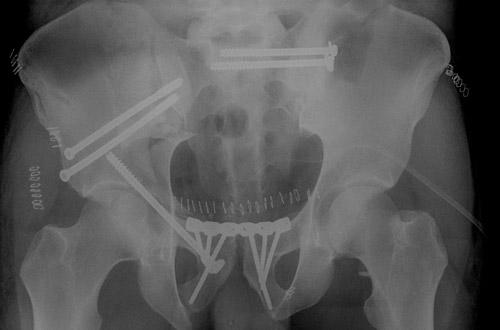

• The posterior pelvic injury was first anatomically reduced and stabilized by two iliosacral screws.

• Then the anterior column of the acetabulum was reduced and stabilised by 2 anteroposterior iliac screws and one retrograde anterior column screw, the symphysis was plated.

First step: Pelvic ring and anterior column fixation